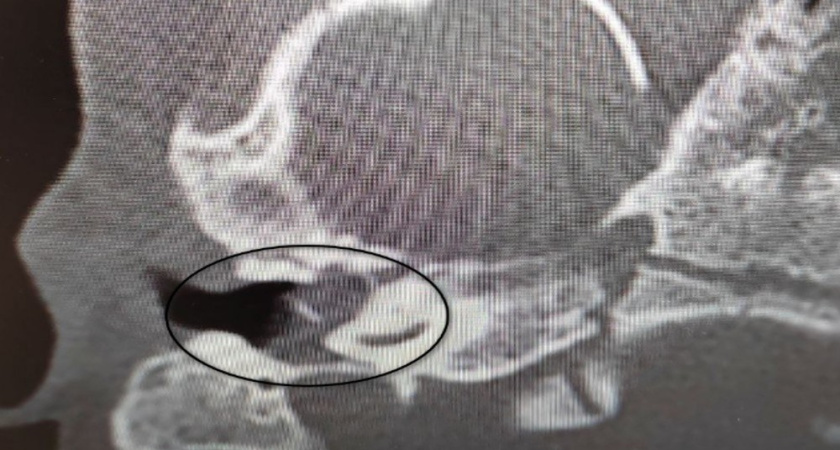

Малышка поступила в оториноларингологическое отделение с хроническим гнойным отитом и подозрением на врождённую холестеатому – кистозное образование, которое разрушает структуры среднего уха и может привести к потере слуха. Такое заболевание встречается крайне редко, особенно у детей младше пяти лет.

После тщательной диагностики специалисты подтвердили диагноз и приняли решение о срочной операции. Заведующий хирургическим отделением Антон Мащенко выполнил сложное вмешательство – удалил опасное образование, провёл декомпрессию лицевого нерва и восстановил звукопроводящий механизм.